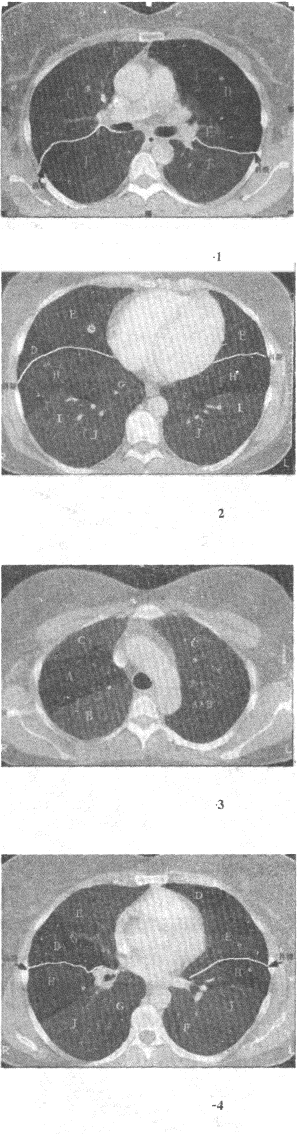

患者男,36岁,低热、咳嗽、咳痰,体重减轻,结合CT图像,最可能的诊断是() 病毒性肺炎。 粟粒型肺结核。 矽肺。 肺转移癌。 细支气管肺泡癌。

结合肺段模式图,选出右肺下叶的组成()